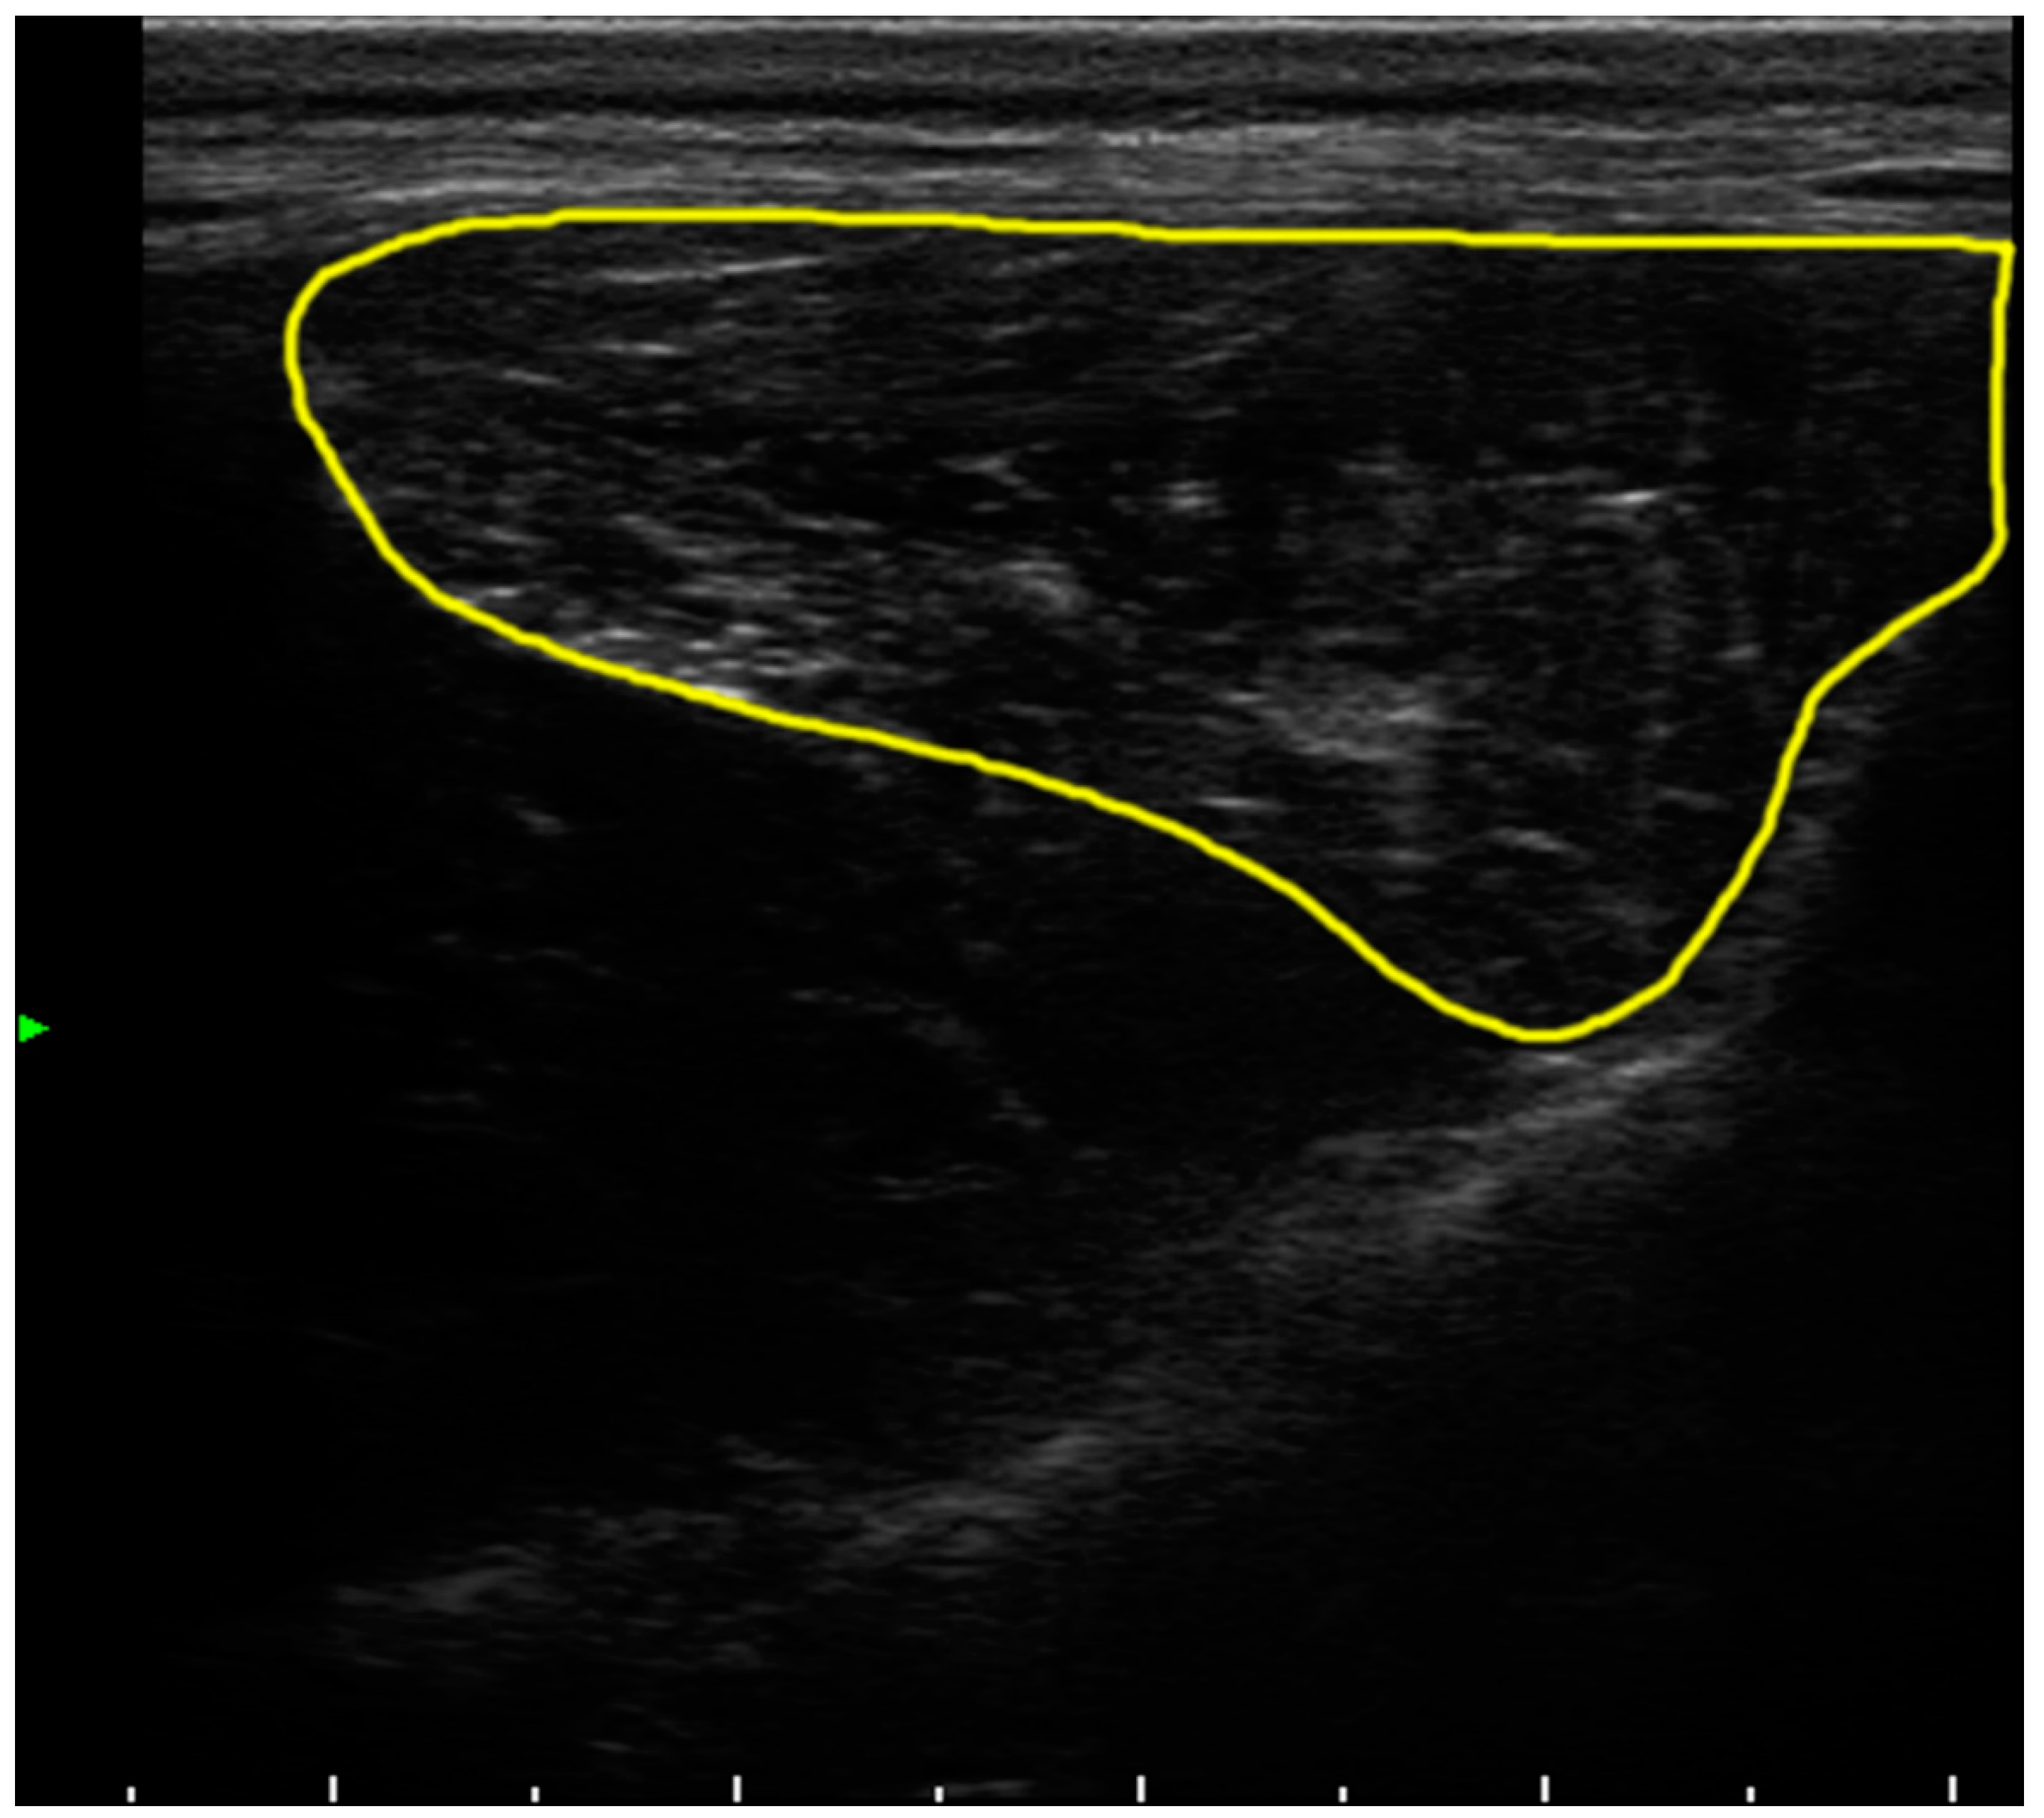

2.3. Computed Tomography and Echography Evaluation

4.4. Muscle Tissue Evaluation by Echography

4.6. Image Processing